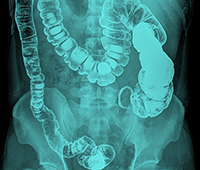

Acid reflux disease - also commonly known as Gastro-esophageal reflux disease (GERD) is condition in which acid from the stomach regurgitates or moves up into the esophagus (gullet).